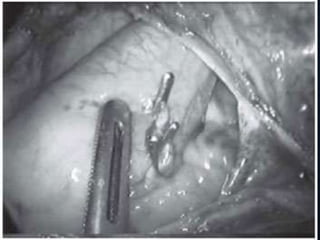

• Outra grande preocupação com segurança está relacionado com

objetos metálicos, tais como clipes cirúrgicos localizados dentro ou

sobre o corpo do paciente.

• O campo magnético pode causar torque ou movimento de torção

do objeto e dano ao tecido que circunda o sitio cirúrgico.

SEGURANÇA – TORQUEDE OBJETOS METÁLICOS • Outra grande preocupação com segurança está relacionado com objetos metálicos, tais como clipes cirúrgicos localizados dentro ou sobre o corpo do paciente. • O campo magnético pode causar torque ou movimento de torção do objeto e dano ao tecido que circunda o sitio cirúrgico. • Pacientes com objetos metálicos estranhos tais como balas, granadas e objetos metálicos intra-oculares têm que ser investigados cuidadosamente.Radiografias convencionais podem ser a solução.